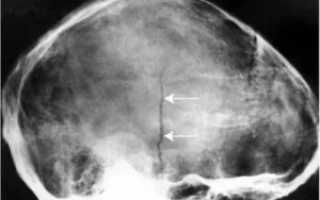

Далее доктор направляет больного на процедуру рентгенографии, которая выполняется в двух проекциях. Если травма является серьезной, то при диагностике тело не меняет своего положения, а передвигается только трубка рентгеновского аппарата.

Томография. Двойной перелом.

Для постановки точного диагноза и составления прогноза выздоровления ребенку проводят рентгенологическое исследование. Краниография позволяет получить четкое изображение, но качественно расшифровать его сможет только опытный врач.

Важно не спутать трещины с сосудистой сеткой и черепными швами. Особенно тяжело отличить трещины, когда они переходят с теменной кости на лобную или затылочную области. Линия разлома имеет черный цвет. Она прямая и узкая без каких либо разветвлений.

При этом сосуды и швы имеют более светлый цвет.

Диагностика перелома теменного сегмента осуществляется с помощью рентгенографического аппарата. Снимок делается в двух проекциях: прямой и боковой.